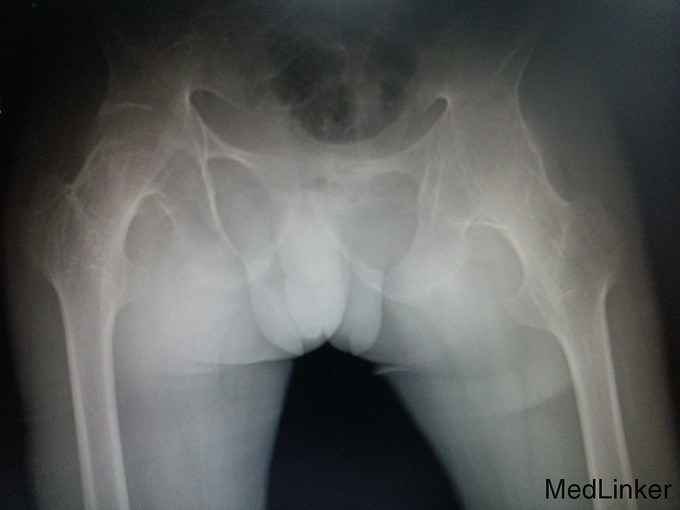

诊断:强直性脊柱炎(累及双侧髋关节) 患者腰骶部活动受限,影像学提示患者双侧骶髂关节间隙消失,且患者HLA—B27异常,强直性脊柱炎诊断明确。患者双髋关节间隙消失,活动度丧失,累及髋关节诊断明确。具有明确手术指症。患者既往关节鳞屑病,现控制稳定,经皮肤科会诊后排出手术禁忌症。由于经济稳定,患者及家属决定分次手术,本次手术暂行右侧人工全髋关节置换术。